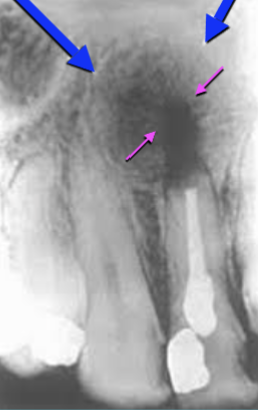

Describe this Radicular Cyst

Epicenter at apex (usually evidence of dental disease or trauma)

Well-defined, corticated

Lucent

Circular

Resorption, Displacement, Expansion (effect on adjacent structures)